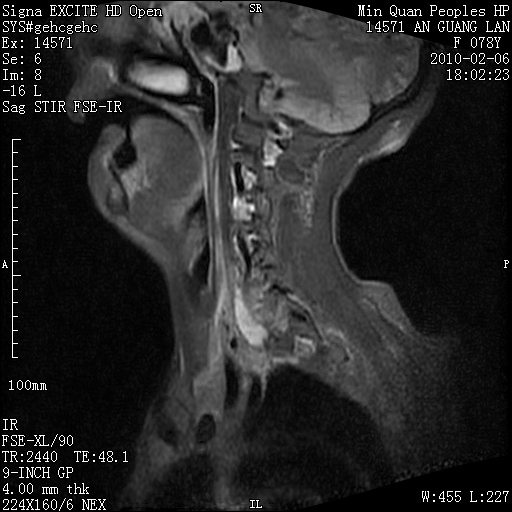

标题: MRI2763:C6、C7椎体病变性质?

f,78y,颈部与双上肢阵发性剧痛40余天。ct可见c6、c7椎体虫蚀样破坏,其间椎间隙变窄(没有图片资料可供上传)。